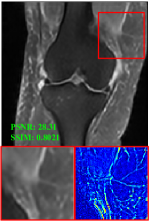

4.3 Qualitative results

Figure 5 provides the qualitative comparison of the various methods on the four datasets at a scale of 4. The top, second, third, and bottom rows are the SR results under the FastMRI, clinical brain, clinical tumor and clinical pelvic datasets, respectively. The red boxes indicate the zoom-in region of complicated anatomical structures along with their corresponding error maps. Note that the brighter textures in the error maps, the lower the quality of the reconstructed images. As can be seen, compared to methods based on Transformers and CNNs, diffusion-based methods like DisC-Diff and DiffMSR (Ours) are capable of reconstructing high-realistic images with promising reconstruction metric scores (PSNR and SSIM). Nevertheless, while DisC-Diff can reconstruct high-precision MR images, it does not preserve the structure present in the original HR images, introducing some additional information that can affect medical diagnosis. In contrast, our method combines DM and PLWformer, which can preserve the original image’s structure while restoring high-frequency information.

9 More Visual Comparisons

In this section, we present more visual qualitative comparisons. Figures 8, 9, 10, and 11 show the reconstruction results of each method in FastMRI, clinical brain, clinical tumor, and clinical pelvic, respectively. As can be seen, although DisC-Diff can reconstruct MR images with high-frequency information, it fails to preserve the structure and content of the original Target HR image effectively, resulting in image distortion. In contrast, our proposed DiffMSR can restore high-frequency information while preserving the structure of the original HR image, indicating the effectiveness of the joint use of DM and PLWformer.